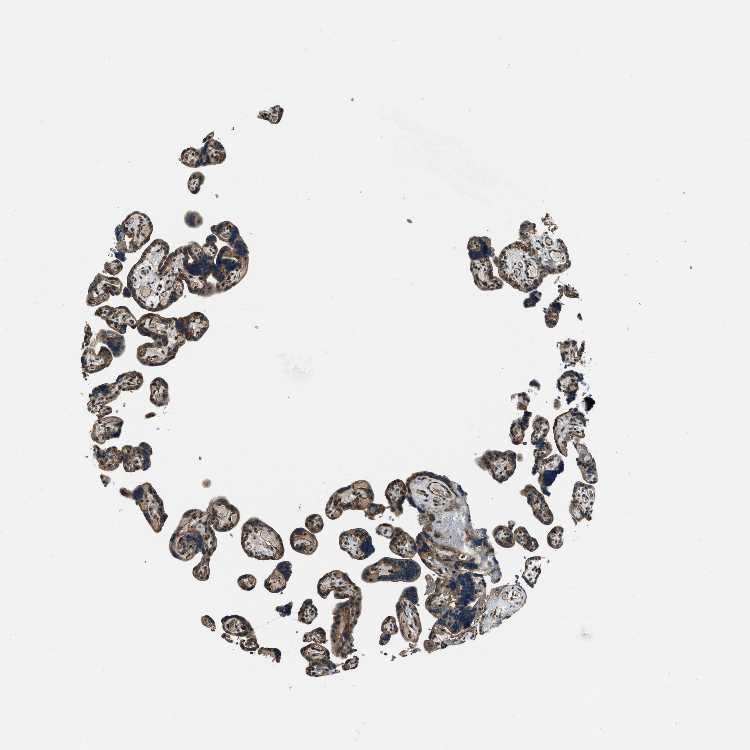

TISSUE PRIMARY DATA PLACENTA Show tissue menu

PLACENTA - Antibody stainingi

Antibody staining in the annotated cell types in the current human tissue is reported as not detected, low, medium, or high, based on conventional immunohistochemistry profiling in selected tissues. This score is based on the combination of the staining intensity and fraction of stained cells.

Each image is clickable and will lead to virtual microscopy that enables deeper exploration of all samples and also displays staining intensity scores, fraction scores and subcellular localization as well as patient and tissue information for each sample.

Antibody HPA020095Antibody HPA020138Antibody CAB010878Antibody CAB080402

Decidual cells MediumMedium-Medium

Trophoblastic cells HighMediumLowNot detected